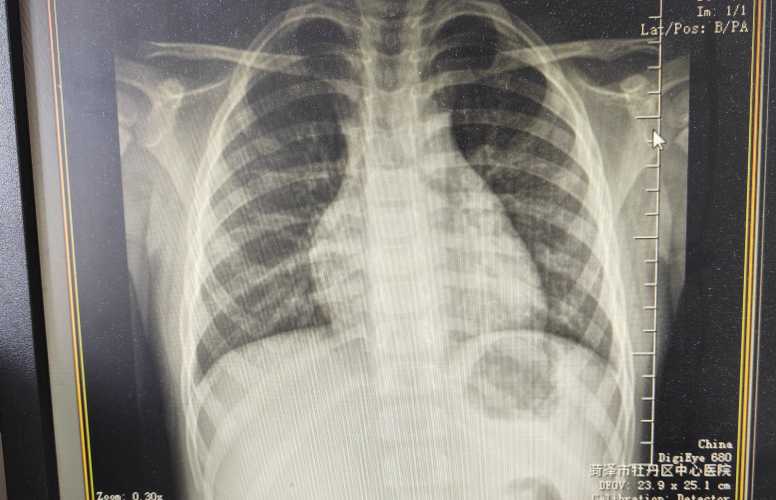

婴儿肺炎可能会发烧 但不是所有宝宝都会烧。我家邻居小孙女8个月得肺炎时烧到39度 脸蛋红扑扑的直哭闹 但上个月我整理读者投稿 有个3个月大的宝宝肺炎 反而没发烧 就有点鼻塞和呛奶 后来呼吸变快才查出来。

一般大点的宝宝得肺炎 发烧的多些 可能38度到39度 烧得高的还会打冷战。但小婴儿或者体质弱的 比如早产儿 可能不发烧 甚至体温偏低 摸起来手脚凉凉的。

宝妈别光盯着烧不烧 更要留意其他信号 像咳嗽变频繁 吃奶时总呛 呼吸明显变快(小婴儿安静时每分钟超过50次) 或者嘴唇发乌 精神蔫蔫的不爱动。我同事家孩子就是 开始只觉得有点咳 没发烧就没在意 后来发现他吸气时锁骨那里凹进去 赶紧送医院 结果是肺炎。

所以宝宝要是咳嗽加重 或者呼吸不对 哪怕没发烧也得往医院跑 别等烧起来才着急。